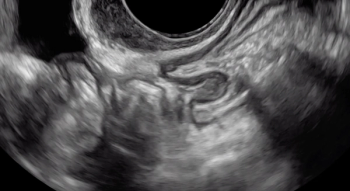

In this clip, fluid within the rectouterine pouch introduced following saline-infusion sonoPODography allows for appreciation of adhesions and a peritoneal pocket (enclosed fluid due to a defect in the peritoneum). These are two classic features of superficial endometriosis.

Although not clearly depicted in this clip, deep endometriosis likely is present posterior to the uterus at the level of the internal cervical os, as demonstrated by the irregular, hypoechoic area.